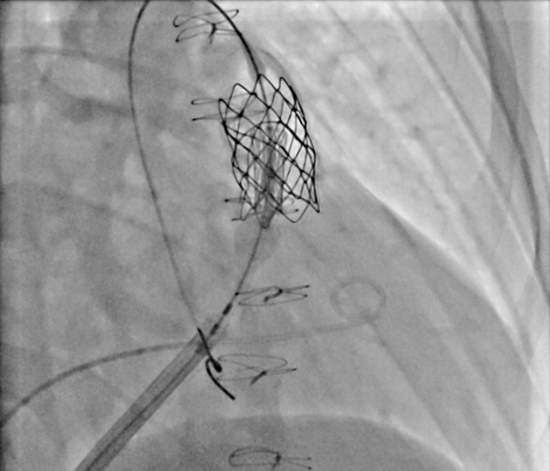

تعبیه موفقیت‌آمیز دریچه شریان ریوی در کت لب بیمارستان فوق تخصصی کودکان حکیم

تعبیه دریچه شریان ریوی Edwards-SAPIEN در نوجوان 16 ساله با موفقیت و بدون جراحی قلب باز در بیمارستان کودکان حکیم انجام شد.

به گزارش روابط‌عمومی بیمارستان فوق‌تخصصی کودکان حکیم دانشگاه علوم پزشکی تهران، مورخ ۱۴ مهر ۱۴۰۴ تعبیه دریچه شریان ریوی Edwards-SAPIEN از طریق آنژیوگرافی در کت لب بیمارستان کودکان حکیم با موفقیت انجام شد. این اقدام در نوجوانی ۱۶ ساله صورت گرفت که به دلیل پرخطر بودن جراحی قلب باز، گزینه غیرجراحی برای درمان وی انتخاب گردید.

تیم مجرب متخصصین قلب، بیهوشی قلب، جراحان قلب و تکنسین‌های اتاق کت لب در انجام این روش پیشرفته همکاری داشتند. در این تکنیک، دریچه شریان ریوی از طریق عروق پا بدون نیاز به باز کردن قفسه سینه تعبیه می‌شود و نسبت به عمل جراحی قلب باز، خطرات کمتری دارد و دوره نقاهت کوتاه‌تری برای بیمار فراهم می‌گردد.

لازم به ذکر است که تعبیه دریچه شریان ریوی نیازمند تجهیزات پیشرفته و مهارت تخصصی می‌باشد و هم‌اکنون این امکان در بیمارستان کودکان حکیم فراهم گردیده است.